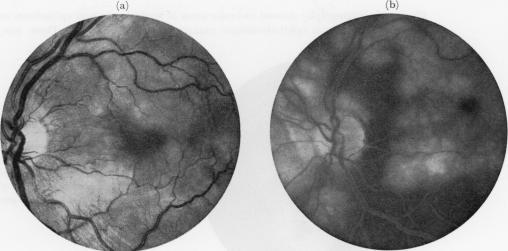

Acute posterior multifocal placoid pigment epitheliopathy. Pigment epitheliopathy of choriocapillaritis?

Br J Ophthalmol. 1972 Dec;56(12):863-74. doi: 10.1136/bjo.56.12.863.